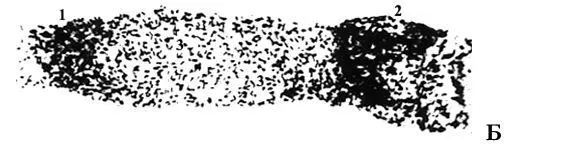

Лимфатический сосуд, тотальный препараты, окрашенные галлоцианином. А (малое увеличение): видна цепь клапанов, над их заслонками сосуд расширяется в разной степени (клапанные синусы с разным наполнением). Б (большое увеличение): 1,2 – входной и выходной клапаны лимфангиона; 3 – область его мышечной манжетки.